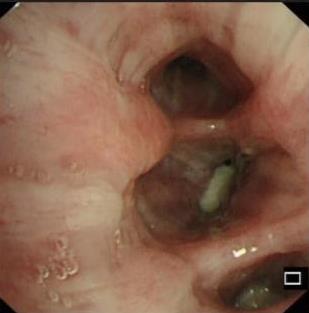

• 侵袭性肺真菌病的支气管镜表现及介入治疗效果

2025, 31(9):81-90. DOI: 10.12235/E20250317

摘要 (112) HTML (56) PDF 6.06 M (77) 评论 (0) 收藏

摘要:目的 探讨侵袭性肺真菌病(IPFD)的支气管镜表现,并评估介入治疗的安全性和疗效。方法 回顾性分析2018年5月12日-2025年5月12日于该院行支气管镜检查的35例IPFD患者的临床资料,观察IPFD的支气管镜表现及介入治疗效果。结果 共收集35例患者临床资料。其中,男22例,女13例,患者年龄(53±14)岁。基础疾病包括:血液系统恶性肿瘤10例,长期应用糖皮质激素者5例,2型糖尿病者4例,肺部恶性肿瘤2例,器官移植1例。胸部CT显示:肺部病变累及单肺叶者19例,累及多肺叶者16例。支气管镜下表现主要为:黏膜充血水肿29例(82.9%)、坏死物堵塞管腔22例(62.9%)、大量黏稠脓性分泌物17例(48.6%)、支气管部分狭窄或闭塞16例(45.7%)、黏膜坏死9例(25.7%)、黏膜出血5例(14.3%)、真菌球3例(8.6%)。其中,32例(91.4%)接受全身性抗真菌治疗,17例(48.6%)接受支气管镜局部两性霉素B灌注治疗,10例(28.6%)采用活检钳钳除病灶,6例(17.1%)采用冷冻探头冻取病灶,4例(11.4%)接受氩气刀治疗。28例(80.0%)临床症状明显改善,肺部影像学病灶缩小或消退;4例(11.4%)病灶稳定;3例(8.6%)未完成治疗。结论 IPFD多见于免疫抑制宿主,支气管镜常表现为:坏死物堵塞管腔、伴脓性分泌物、支气管管腔狭窄和局部黏膜充血水肿或坏死。全身抗真菌药物联合支气管镜下介入治疗,安全性高,且疗效好。